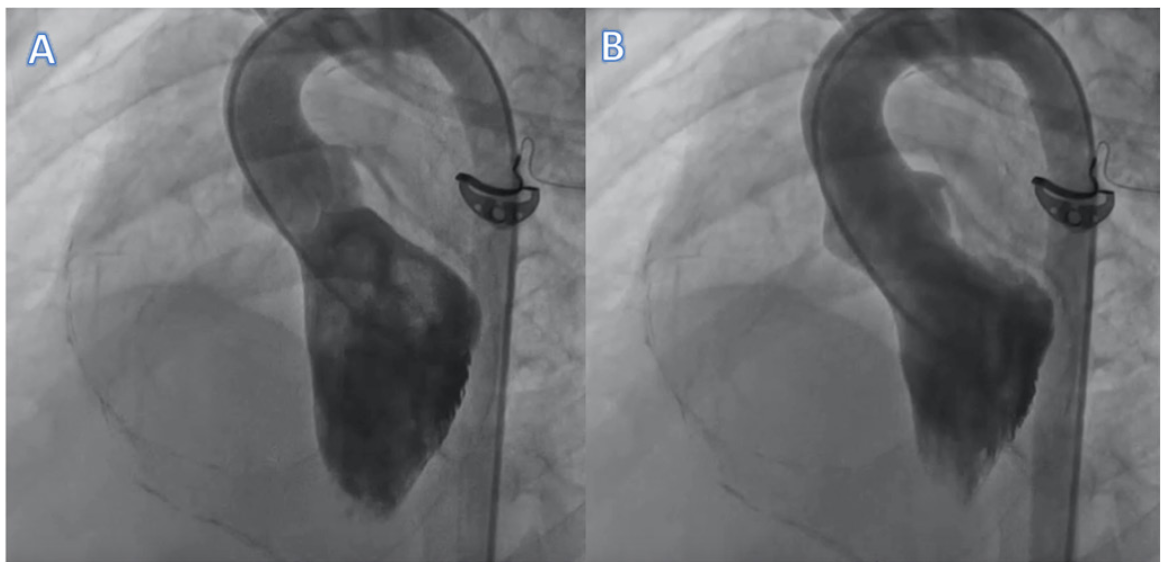

A 14-year-old boy presented with dyspnea on exertion and easy fatiguability for 1 year. He also had an episode of pedal edema 6 months prior, which resolved with diuretics. He had a history of tuberculosis treated with a 6-month course of antitubercular therapy. On examination, he had a loud pulmonary component of second heart sound and an added heart sound. Jugular venous pressure was elevated. After echocardiography, the patient was taken for cardiac catheterization. A left ventricular angiogram was performed during catheterization (Figure 1 and Video 1). The left ventricular angiography showed mild reduction in ventricular systolic function. On detailed analysis, it is evident that longitudinal contraction of the left ventricle is preserved, whereas the circumferential contraction is severely impaired. Pericardial calcification also can be seen encircling the left and right ventricles (Figure 2). Echocardiography showed that the patient had moderate pulmonary hypertension and features suggestive of constrictive pericarditis. In restrictive cardiomyopathy, the longitudinal contraction is impaired whereas the circumferential contraction is preserved. In dilated cardiomyopathy, the left ventricle is dilated. There is obliteration of the left ventricular cavity during systole in cases of hypertrophic cardiomyopathy. Pericardial calcification is evident in around 25% of cases of constrictive pericarditis and predominantly seen in those with tubercular and pyogenic etiology. The subepicardial myocardial fibers are responsible for radial shortening and subendocardial fibers are responsible for longitudinal shortening. In constrictive pericarditis, the involvement of the subepicardial fibers leads to reduction in the circumferential shortening. The patient was referred for pericardiectomy.